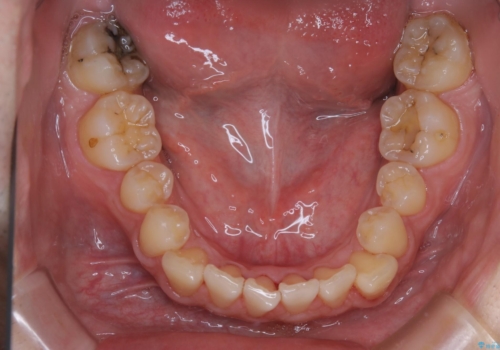

人生で初めてのクリーニングということもあり、プラークや歯石が大量に付いていました。それにより、歯茎の腫れもあり出血も多かったです。これから矯正をスタートしていくため、歯ブラシ指導を行いホームケアを頑張ってもらっています。